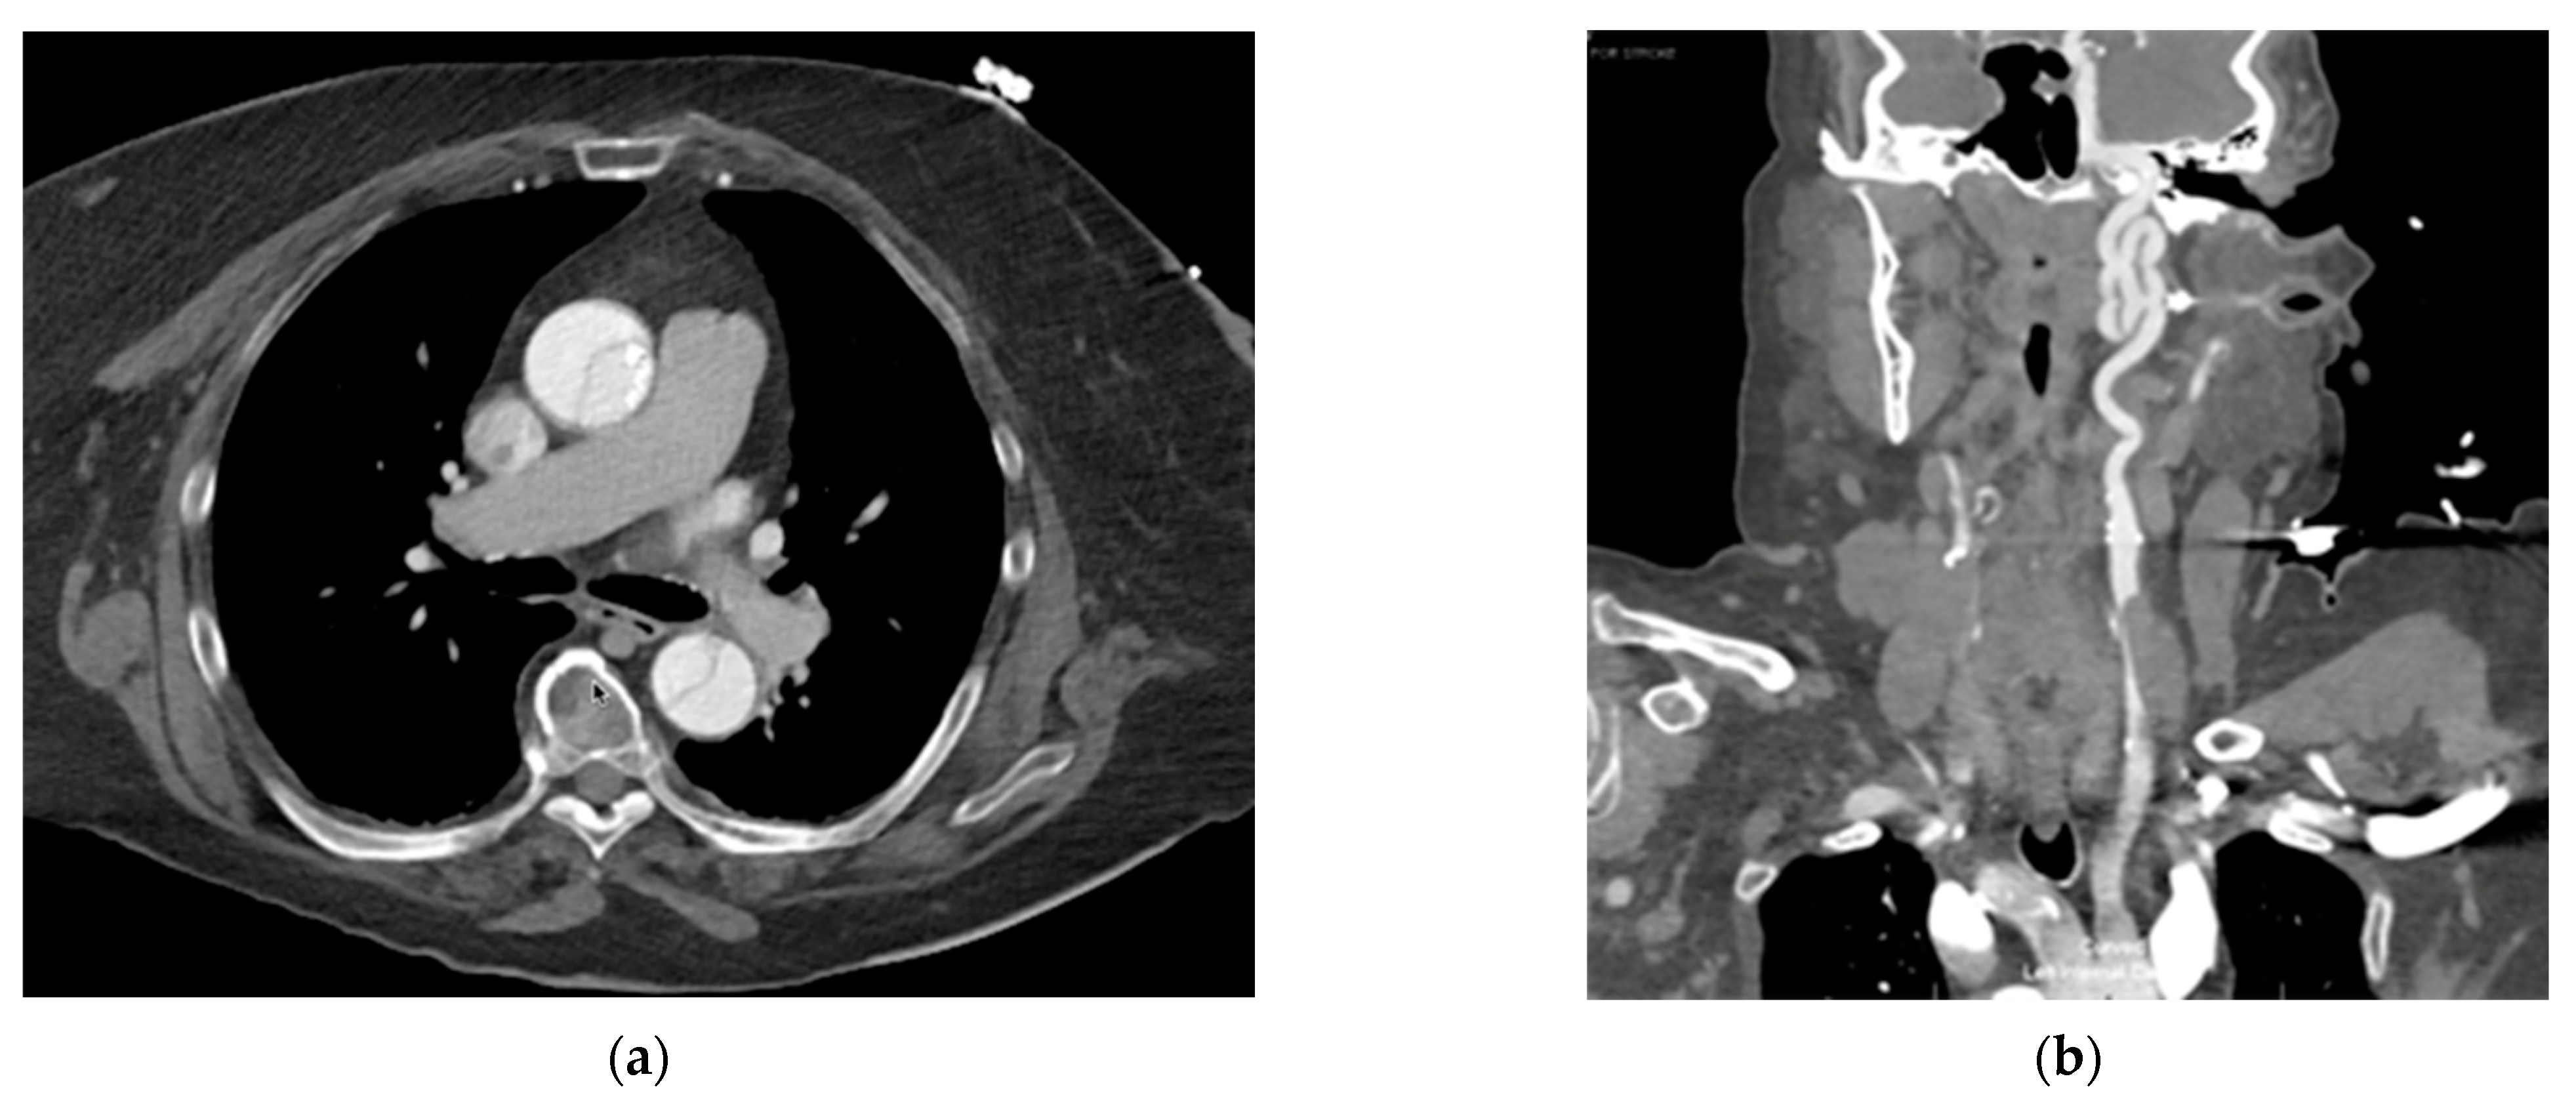

2. Detailed Case Description

3.4. Type A Aortic Dissection